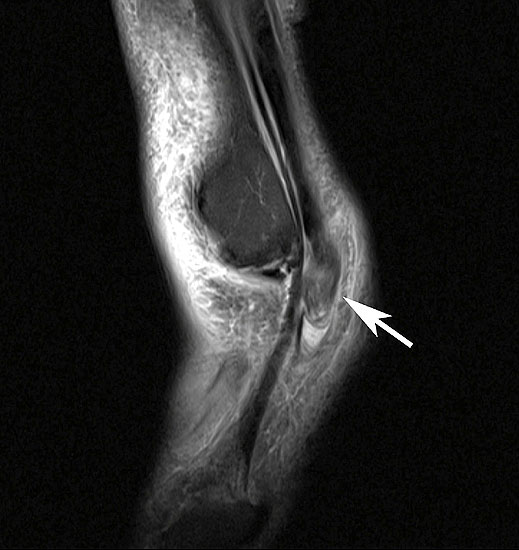

Ruptur der Peronaeus longus Sehne mit proximalisiertem Sehnenstumpf im MRT

Abbildung 14

Die akute vollständige Ruptur betrifft in der Mehrzahl der Fälle die Peronaeus longus Sehne, typischerweise in Höhe des Kuboid-Tunnels 40. Die Patienten berichten über ein geräuschvolles Reißen der Sehne mit anschließenden Schmerzen am lateralen Fußrand. Klinisch besteht eine Schwellung und Druckschmerzhaftigkeit im Sehnenverlauf. Die Plantarflexion und die Eversion des Fußes gegen Widerstand ist schmerzhaft 41. Bei einer kompletten Ruptur der Peronaeus longus Sehne kann es zu einem Ausriss des Os peronaeum kommen, dieses kann bis in Höhe des Außenknöchels dislozieren. Zur Beurteilung der Sehne ist das MRT mit Kontrastmittel das Verfahren der ersten Wahl.